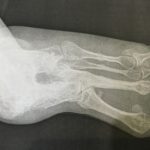

po operacji